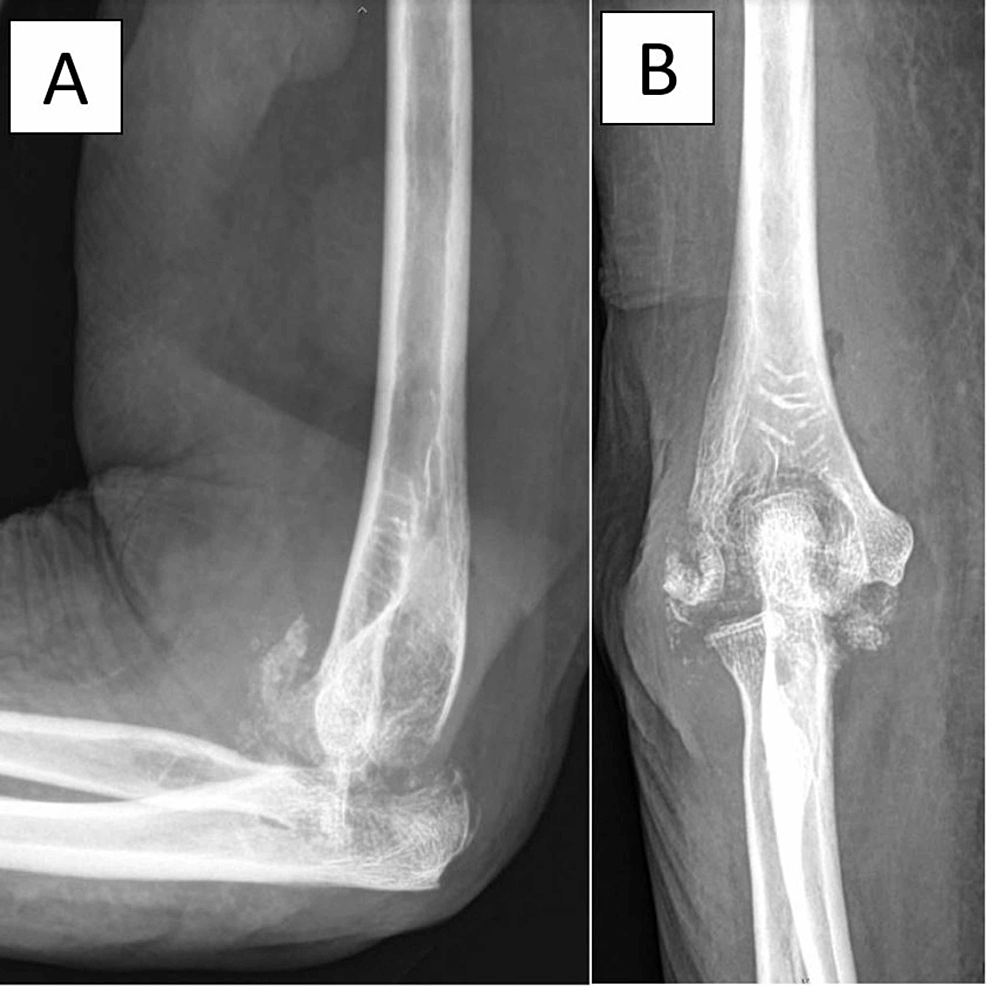

Клинический случай туберкулезного поражения сустава, который продолжался на протяжении 5 месяцев и привел к деструкции сустава.

Разрушение кости при туберкулезном артрите.

- Рентгенография - в основном для исключение перелома (если была травма), определения стадии деструкции сустава.